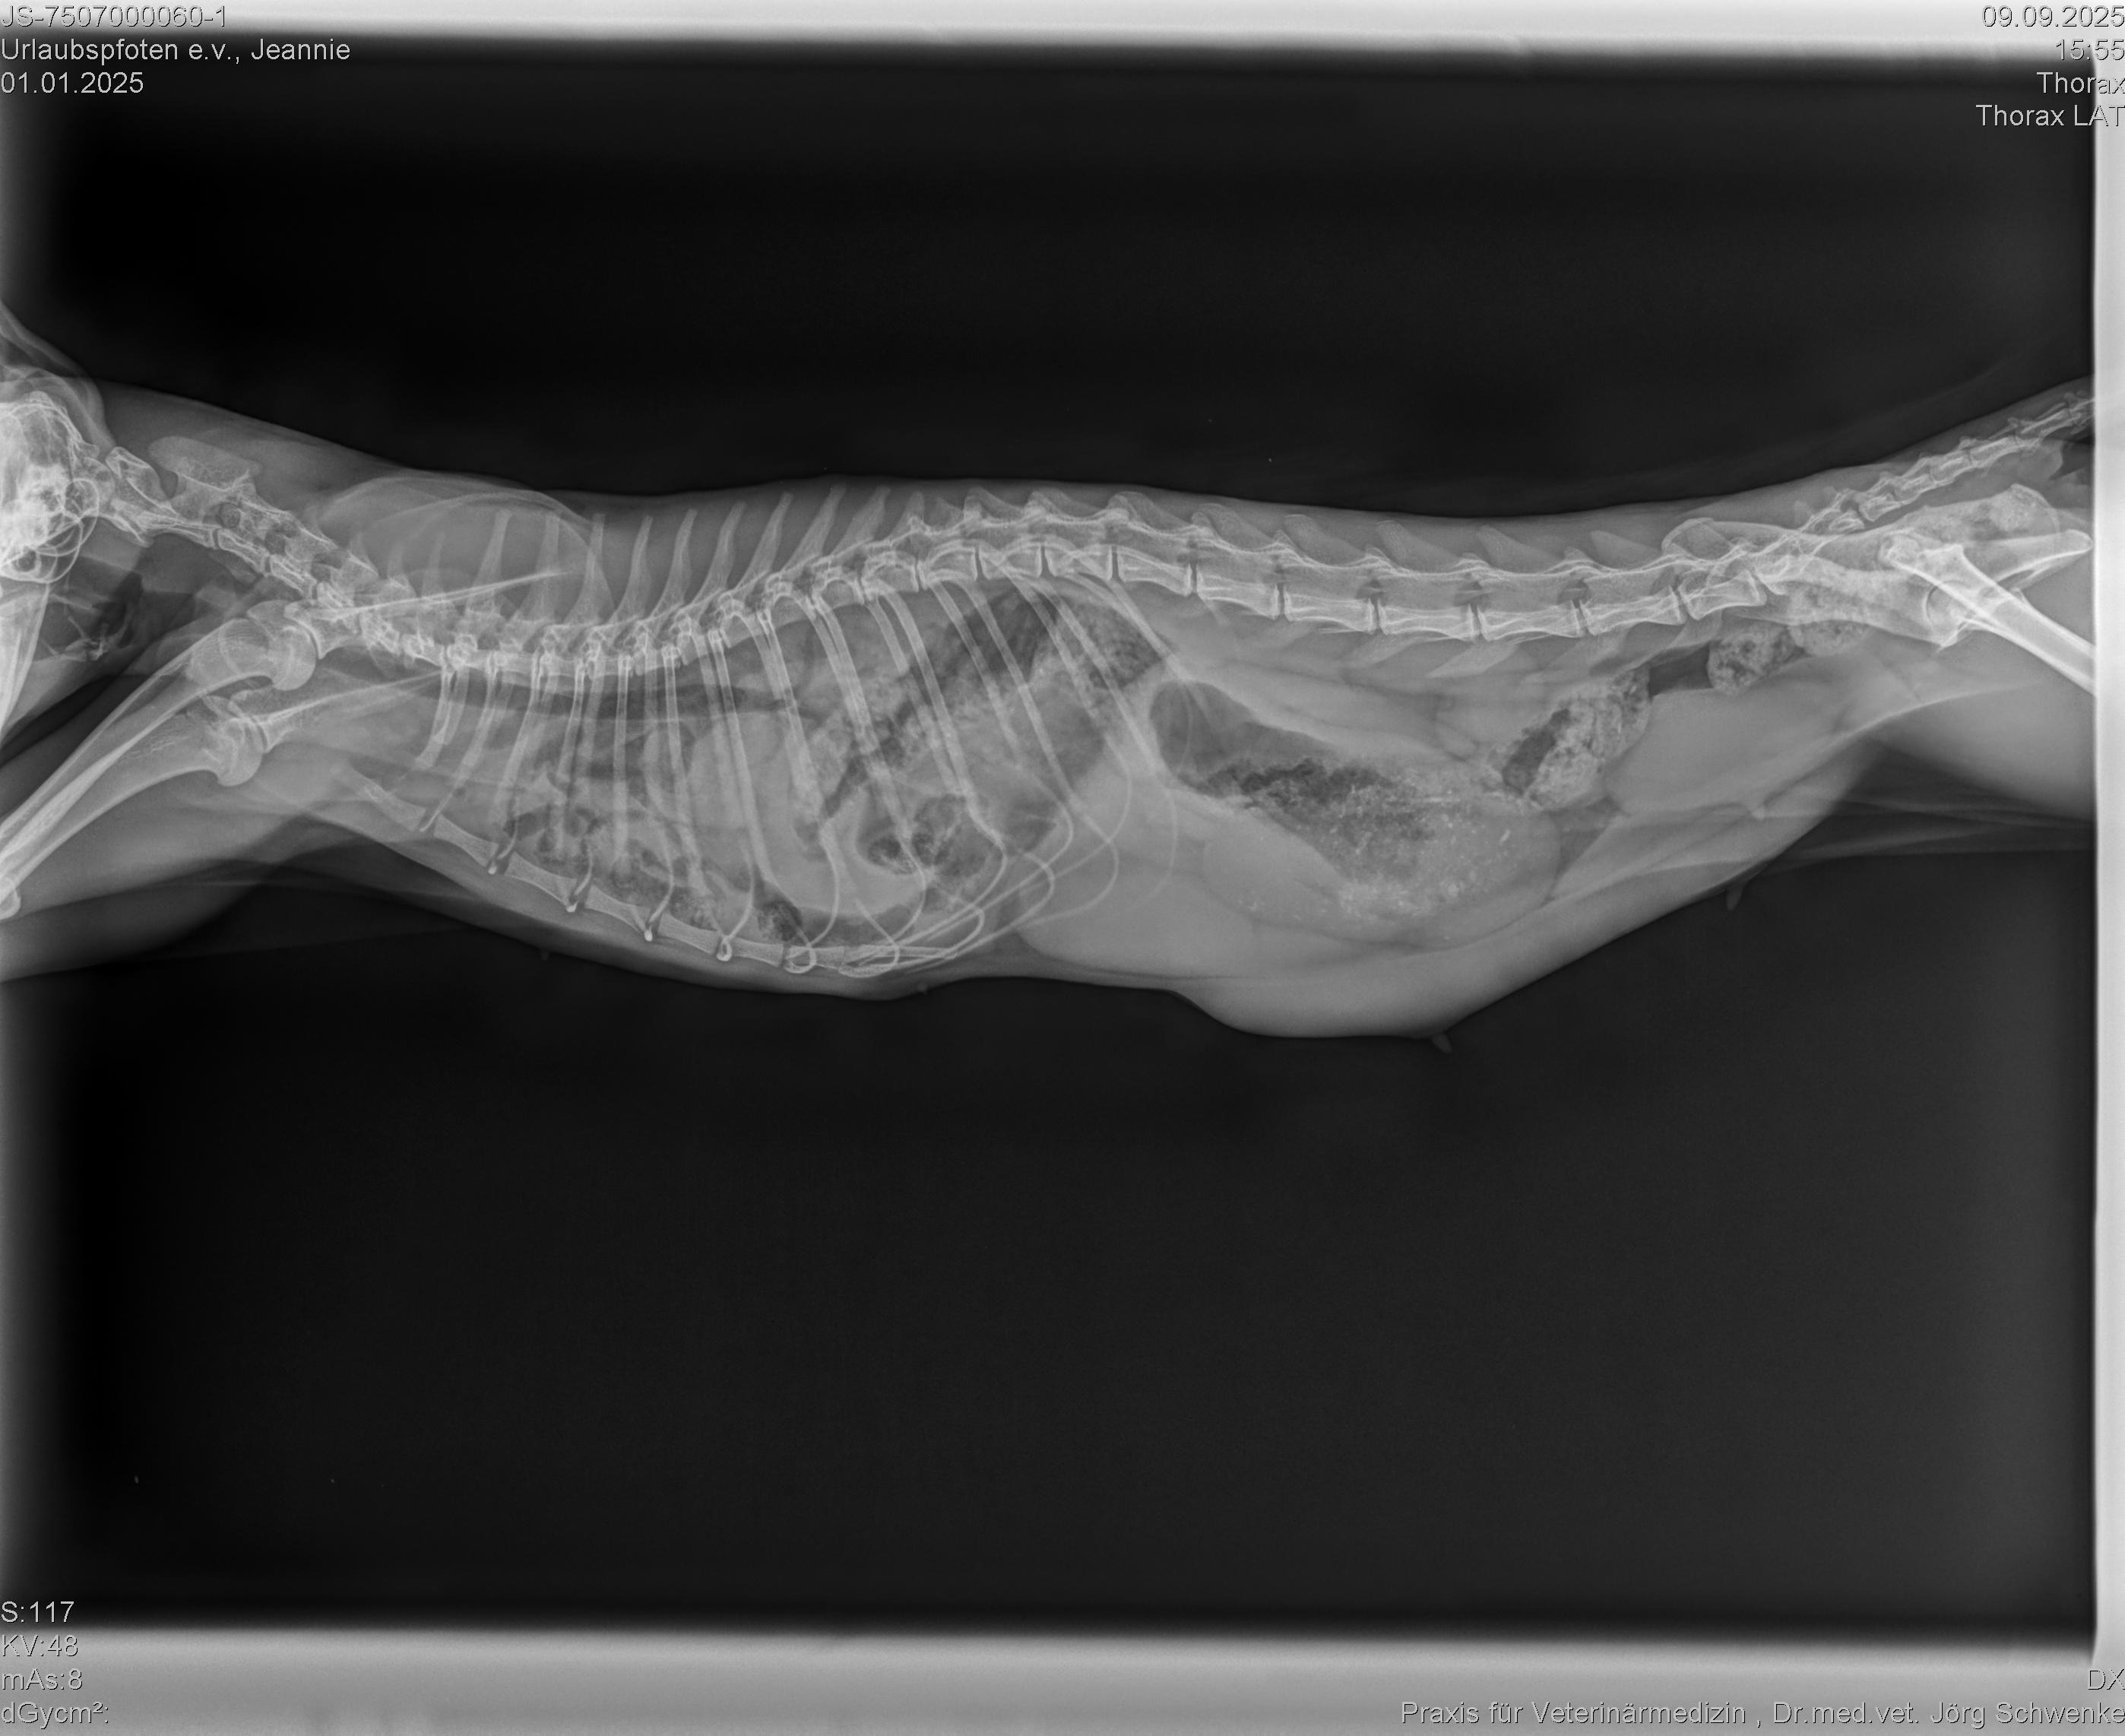

Jeannie, eine knapp einjährige Mutterkatze, hat eine Zwerchfellhernie, die dringend operiert werden muss. Was ist eine Zwerchfellhernie? Das ist ein Zustand, bei dem sich der Magen oder andere Bauchorgane durch eine Lücke oder einen Defekt im Zwerchfell in den Brustkorb verlagern. Sie bekommt ganz schlecht Luft, ist immer erschöpft und kann nur winzige Menge Futter zu sich nehmen. Wir, der Verein Urlaubspfoten e.V., haben Jeannie und ihre beiden Kitten Chip und Chap an einem Futterplatz sichern können. Dazu war wochenlange Vertrauensarbeit notwendig, bis die Kleinen gross genug waren und Jeannie sie nicht mehr verstecken konnte. Trotz ihrer schweren Beeinträchtigung hat es diese bezaubernde Katze irgendwie geschafft ihre Babies auf die Welt zu bringen, zu säugen und zu versorgen. Sie selbst blieb dabei fast auf der Strecke und ohne diese lebensnotwendige OP hat sie keine lange Lebenserwartung. Wir wollen ihr diese Chance gerne ermöglichen, brauchen dazu aber EURE HILFE!